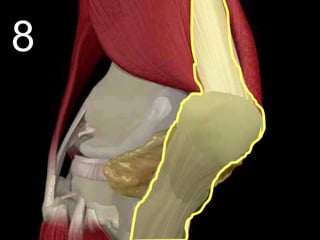

 Hinge Joint: Allows extension and retraction.

Long Bone